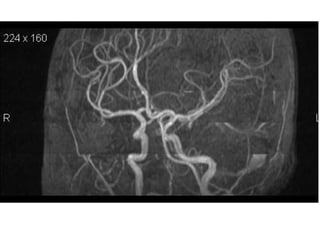

6- MRA demonstrate

stenosis of -

1- vertebral artery

2- basilar artery

3- PICA

4- AICA